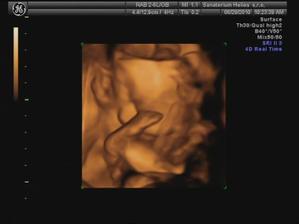

29.6. jdeme na 3D ultrazvuk 🙂 těšíme se... - bylo to úžasný 🙂 cena sice vyšší, ale jedna barevná fotka tištěná, 3 fotky na mail a téměř půlhodinové video, ze kterého jsme si doma udělali ještě asi 120 fotek 🙂